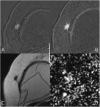

Due to its superior sensitivity, breast MRI (bMRI) has been established as an important additional diagnostic tool in the breast clinic and is used for screening in patients with an elevated risk for breast cancer. Breast MRI, however, is a complex tool, providing multiple images containing several contrasts. Thus, reading bMRI requires a structured approach. A lack of structure will increase the rate of false-positive findings and sacrifice most of the advantages of bMRI as additional work-up will be required. While the BI-RADS (Breast Imaging Reporting And Data System) lexicon is a major step toward standardised and structured reporting, it does not provide a clinical decision rule with which to guide diagnostic decisions. Such a clinical decision rule, however, is provided by the Kaiser score, which combines five independent diagnostic BI-RADS lexicon criteria (margins, SI-time curve type, internal enhancement and presence of oedema) in an intuitive flowchart. The resulting score provides probabilities of malignancy that can be used for evidence-based decision-making in the breast clinic. Notably, considerable benefits have been demonstrated for radiologists with initial and intermediate experience in bMRI. This pictorial essay is a practical guide to the application of the Kaiser score in the interpretation of breast MRI examinations.